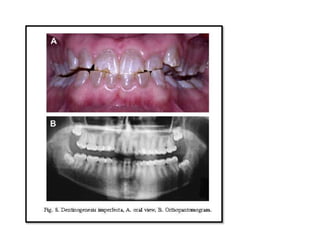

Fig. 3. Amelogenesis imperfecta hypoplastic

generalized: A. oral view, B.

orthopantomogram.

Fig. 3. Amelogenesisimperfecta hypoplastic generalized: A. oral view, B. orthopantomogram.